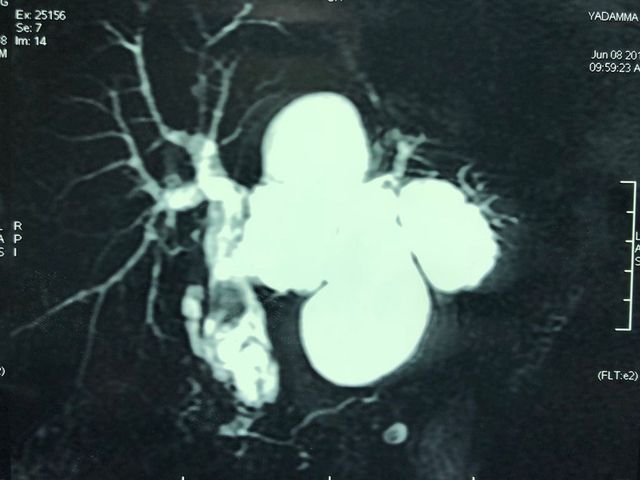

Recurrent pyogenic cholangitis (RPC) - 67 yr old Bangladeshi lady presented with recurrent episodes of jaundice, fever and pain for past 1 year

Interesting images: Recurrent pyogenic cholangitis (RPC) 67 yr old Bangladeshi lady presented with recurrent episodes of jaundice fever and pain for past 1 year. MRCP and CT scan showed left duct stricture with left sided IHBRD and CBD stones and atrophy of left lateral segment. As she 4 duct was also involved we did a left hepatectomy with hepaticoduodenostomy . Reccurant pyogenic cholangitis is a disease charecterised by multiple instances of biliary bacterial infection, hepatic abcesses , multiple stricturing of bile ducts with pigment stone formation in the intrahepatic and extrahepatic biliary tree. This can cause reccurant episodes of cholangitis, chronic illness ultimately leading to liver failure. It is more common in the far east population. Management includes long term biiary drainage with liver resections for segmental disease and liver transplantation in patients with end stage liver failure . The last CT scan shows another CT scan another similar patient with huge intrahepatic stones and abscesses managed successfully by surgery and long term PTBD.